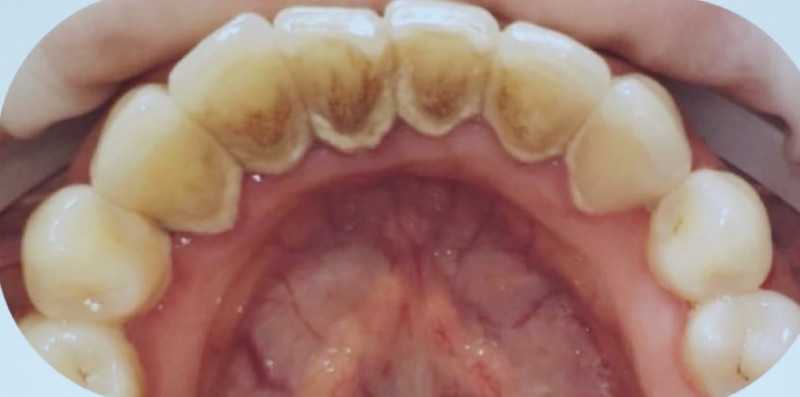

Профгигиена

Доктор: Попова (Михеева) Юлия Васильевна

Доктор: Новлянцева (Новосад) Екатерина Игоревна